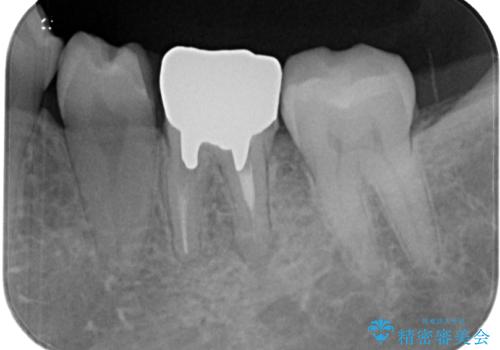

- 近医にて抜歯が必要と診断されたとのことで来院された患者様です。

術前の診査では、歯が破折している可能性が高いものの、確実に抜歯が必要と診断ができない状態でした。

状況次第では抜歯が必要となり、その際にはインプラント治療を行うことを了承いただいた上で、破折していない場合には根管治療を行うこととしました。

土台の材料を外して顕微鏡下で確認したところ、歯根にまで及ぶ破折が認められたため、インプラント治療を行うこととしました。